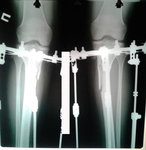

рентген в 60 дней.

Сращение идёт хорошо. Делаем рентген в 90 дней и готовимся к снятию.